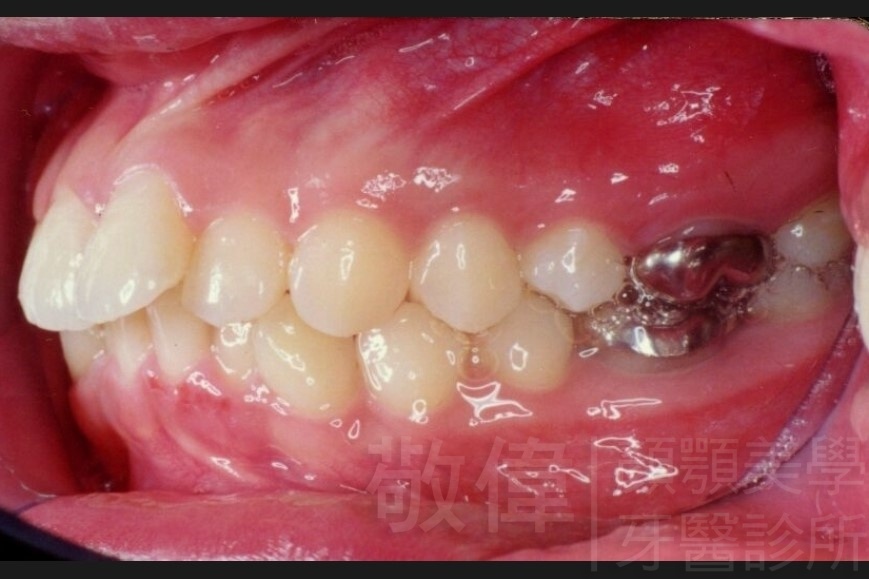

齒顏矯正/上顎暴牙且牙齒極度混亂

矯正前-右   矯正前-正   矯正前-左

矯正後-右   矯正後-正   矯正後-左

<個案說明>

上顎暴牙且牙齒極度混亂,經由矯正之後,臉型大幅度改善,牙齒的排列更加的整齊健康。相較於之前眼神充滿精神,自信心展現無遺。